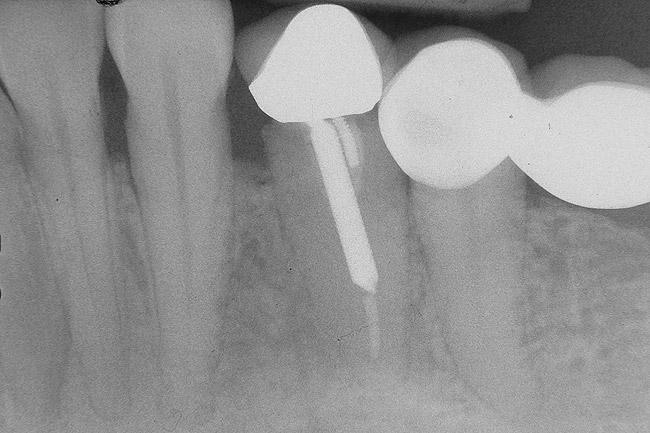

Figure 6   Tooth No. 29 with the temporary build-up close to the osseous crest. Tooth No. 29 has a short post, and tooth No. 31 has a very short root trunk.

Figure 6

Figure 7  Condition of the teeth seen in Figure 6, approximately 5 years after restoration. Note the extensive furcation involvement of tooth No. 31 and its residual periapical radiolucency.

Figure 7

Figure 8  Same case as in Figure 7 showing teeth Nos. 28 and 29. Note that tooth No. 28 was included into the four-unit restoration, and the small radiolucency on the distal tooth No. 29, which was associated with a root fracture.

Figure 8

The clinician also must consider the status of the adjacent teeth. Figure 6 shows teeth Nos. 29 and 31 prepared for a fixed bridge. Factors to be considered in this example were the short root of tooth No. 29 with a distal biologic width violation and a short root trunk on tooth No. 31 (which leads to furcation involvement with a small amount of facial or lingual bone loss). This patient also had periodontal disease, which further decreased the long-term prognosis of the fixed bridge option. No prospective studies directly compare the longevity of the two options: a three-unit fixed bridge vs an implant.37 Other factors that complicate comparisons of an implant vs a fixed three-unit bridge are the variability of fixed bridges as well as the variability of the implants (amount of bone, implant length, etc). For example, endodontically treated abutment teeth do not last as long as nonendodontically treated abutment teeth.38 Restorations on teeth with endodontic posts and a minimal length of ferrule do not persist as long as those on teeth without a post and at least a 2-mm ferrule.39

In this example, the more predictable option would have been to place an implant in the No. 30 position and restore the area as three single units. However, the treatment delivered involved a four-unit fixed bridge, which then included tooth No. 28. Unfortunately, this bridge failed at approximately 5 years (Figure 7 and Figure 8) because of a root fracture of tooth No. 29 and advanced furcation involvement with residual endodontic infection of tooth No. 30. The inclusion of tooth No. 28 into the bridge also decreased its long-term prognosis because of its preparation.43 The alternative restorative option of a RPD also would decrease the prognosis of the RPD abutment teeth, which fail more often than FPD abutment teeth.43